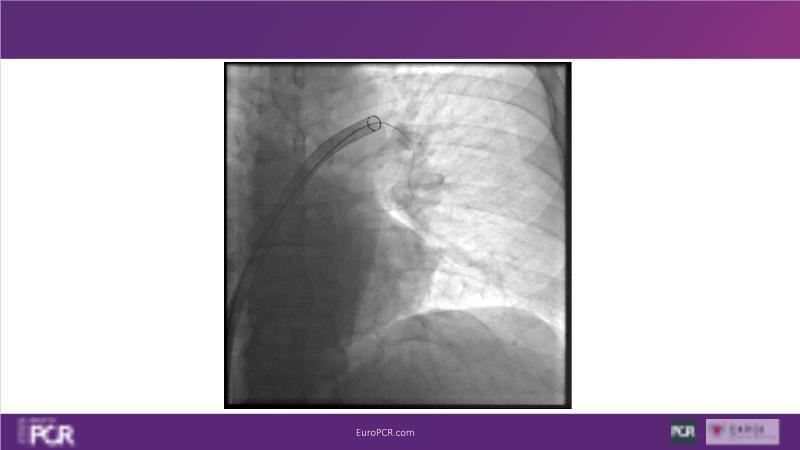

Why mechanical thrombectomy should be considered in the management of acute pulmonary embolism

In this EuroPCR 2024 session, study the case of a patient with high-risk pulmonary embolism and another with intermediate to high-risk pulmonary embolism, delve into discussions on clinical evidence for mechanical thrombectomy in pulmonary embolism, acquire skills to evaluate eligibility for mechanical thrombectomy, and learn how to integrate such technique in local pulmonary embolism patient pathway.